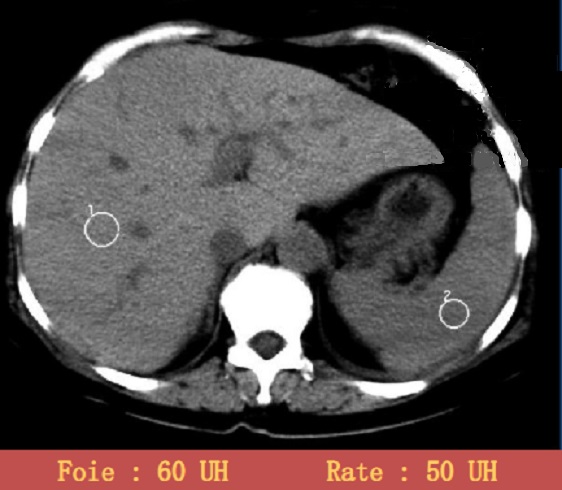

Image radiologique TDM

moindre densite ( 50 UI ) que le foie ( 60UI )

. Image radiologique TDM en coupe axial |